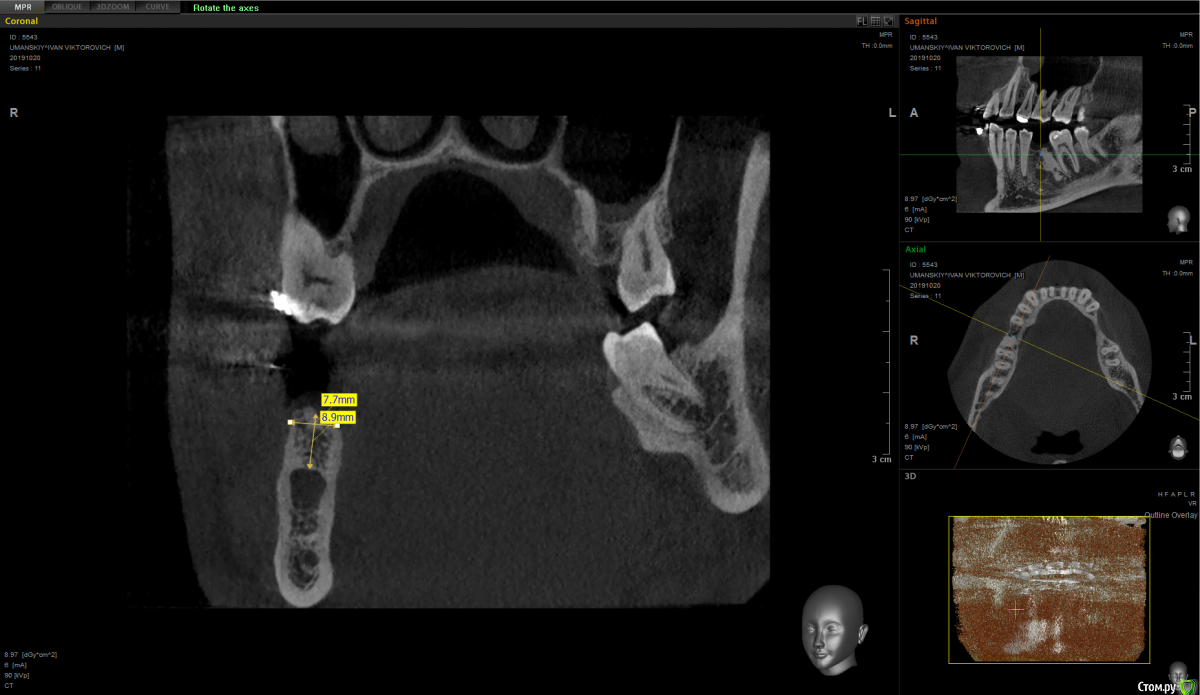

Raystom Опубликовано 16 мая, 2021 Поделиться Опубликовано 16 мая, 2021 (изменено) На общей ниве задам вопрос. Как правильно поступить, засверлиться медиальнее или засверлиться, ушить, подождать 3 недели и установить имплантат. Со слов в этом месте 1.5 года назад удаляли резорциненный 36. По КТ не видно рельефа кости в общем и есть эностоз в середине. Ортодонтически пытались двигать 37, 38 вперёд - не выходит. Изменено 16 мая, 2021 пользователем Raystom Ссылка на комментарий

It'sGeorgy Опубликовано 16 мая, 2021 Автор Поделиться Опубликовано 16 мая, 2021 Вы вот так ставить планируете? Если да, то, имхо, немного смысла в предварительном препарировании. Вы весь этот остеоид высверлите практически. Ссылка на комментарий

Raystom Опубликовано 16 мая, 2021 Поделиться Опубликовано 16 мая, 2021 В том-то и дело, что не весь, а дистальная стенка имплантата будет в контакте с образованием Ссылка на комментарий

Женька Опубликовано 16 мая, 2021 Поделиться Опубликовано 16 мая, 2021 Это же кость, разве нет? почему бы не относится к ней как к кортикальному слою? Ссылка на комментарий

Raystom Опубликовано 16 мая, 2021 Поделиться Опубликовано 16 мая, 2021 2 часа назад, Женька сказал: Это же кость, разве нет? почему бы не относится к ней как к кортикальному слою? В принципе так и думал, но смущает пару моментов, получу ли я не только механическую стабильность, а ещё и последующую интеграцию при одномоментном подходе и смущает островок плотной кости на фоне крупноячеистой кости. В остальных участках кость выглядит как D2 на всем протяжении Ссылка на комментарий